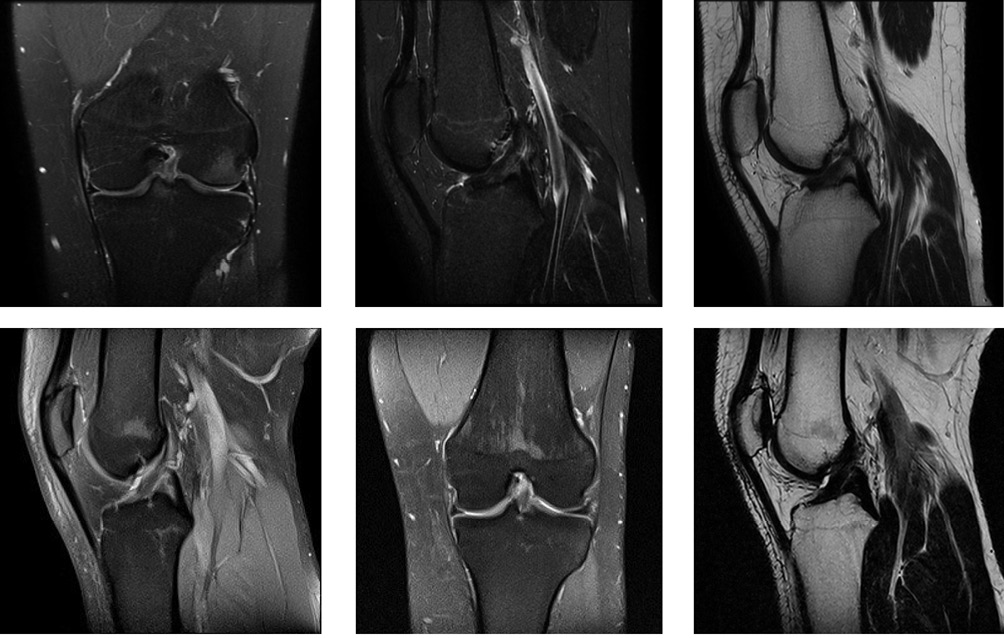

History of Present Illness. In March 2025, during training, the patient sustained a left knee injury due to a fall. Given the trauma and severe pain, magnetic resonance imaging (MRI) of the injured joint was performed outpatient at the local clinic. The MRI findings indicated an isolated ACL injury of the left knee joint (Fig. 2A). Two days post-injury, the patient was examined by a trauma orthopedist at the Federal Scientific and Clinical Center for Children and Adolescents.

The follow-up examination six months after the injury showed the ability of the patient to walk independently and confidently, without limping. No edema in the left knee joint area was present; the patella was in the midline. Ballottement sign was negative, Lachman and anterior drawer tests were negative, symmetrical on both sides. No subjective or objective signs of knee joint instability were detected, VAS was 0 points. Therefore, according to control MRI data, restoration of the anterior cruciate ligament structure was confirmed (Fig. 2B).

MRI image obtained by the authors.

Fig. 2. Magnetic resonance imaging of the left knee joint: A — after injury; B — after treatment